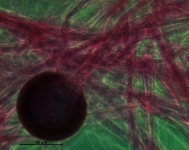

| Species Name: | Rhizopus microsporus var. rhizopodiformis |

| Taxonomy: | FUNGI Mucoromycota, Mucoromycetes, Mucorales, Rhizopodaceae |

| Characters: | CULTURE CONDITIONS short sporangiophores, finely roughened spores, well developed rhizoids and high temperature tolerance - // MOLECULAR SYSTEMATICS identified as Rhizopus microsporus var. rhizopodiformis based on D1D2 blast result and on phenotypic characteristics - fide UAMH 2012 // THERMOTOLERANT grows at 50, NG at 55C - fide submitting lab (Click for publications citing UAMH 11643) |